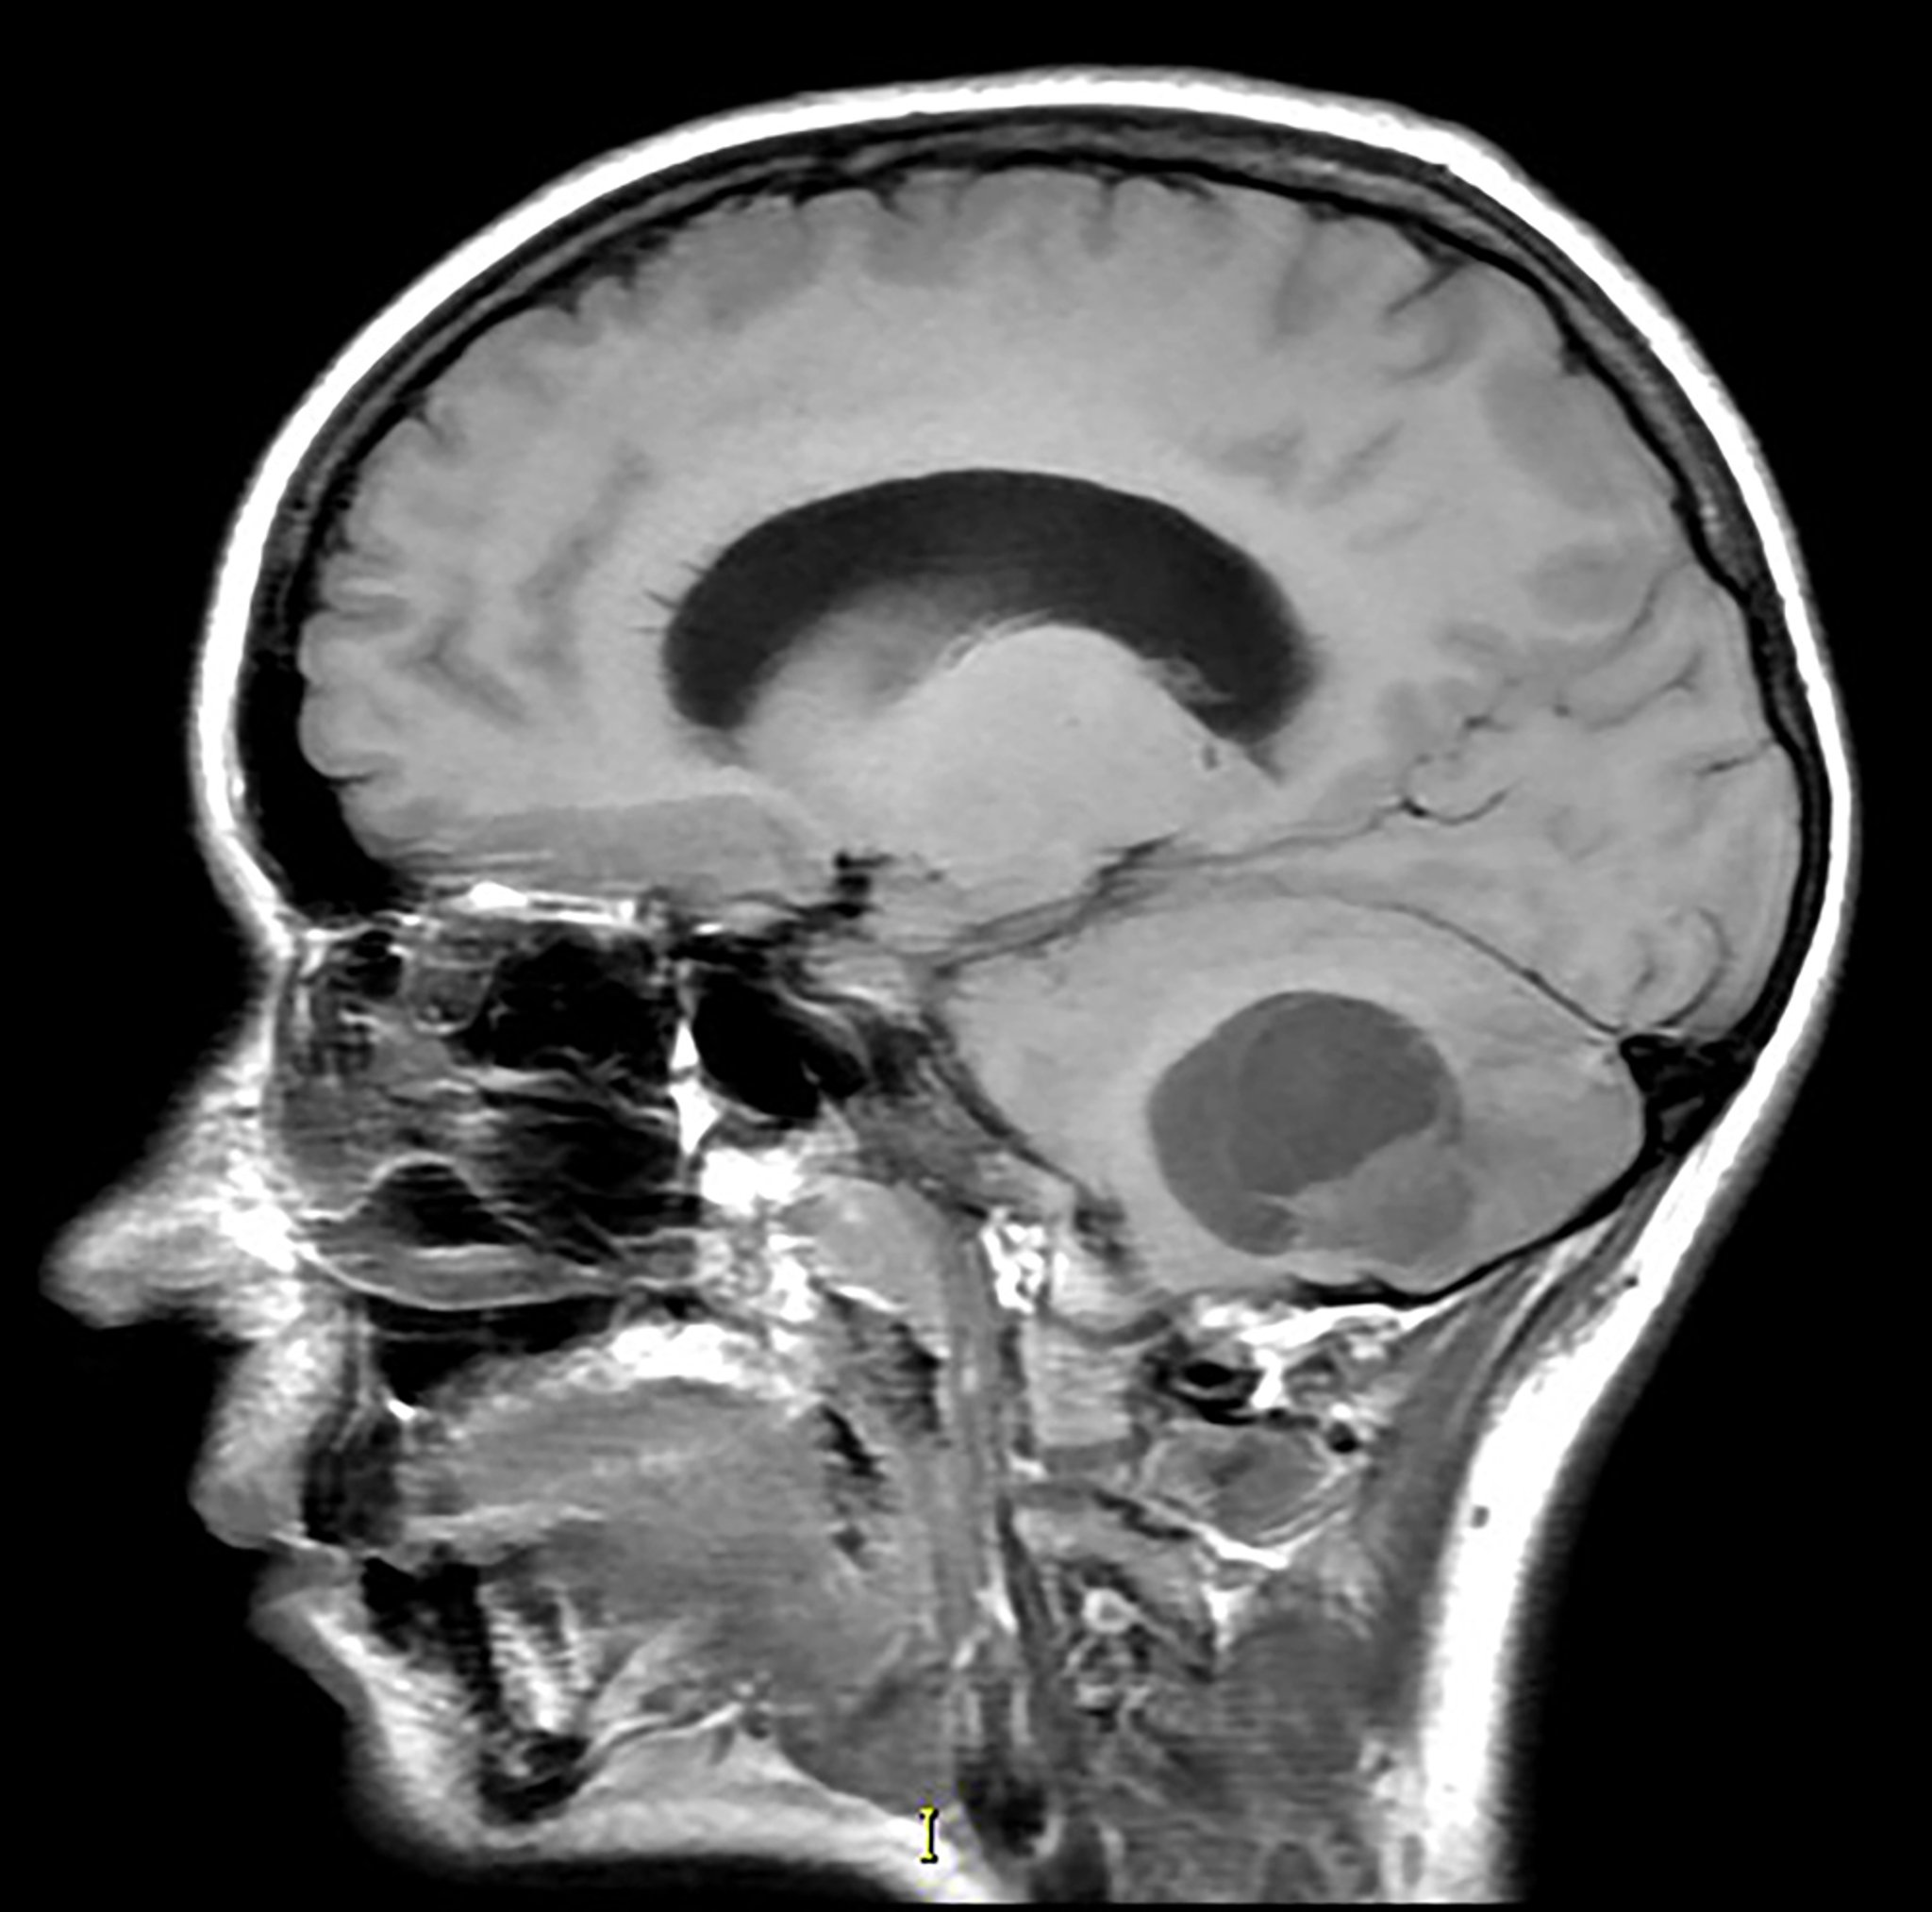

Мозжечковая гемангиобластома (МРТ)

На этом сагиттальном Т1-взвешенном магнитно-резонансном изображении без контраста видно частично кистозное и солидное образование в нижней части мозжечка с сопутствующим масс-эффектом. Это наиболее распространенный внешний вид гемангиобластомы. Эта опухоль с большей частотой наблюдается у пациентов с синдромом Гиппеля-Линдау.